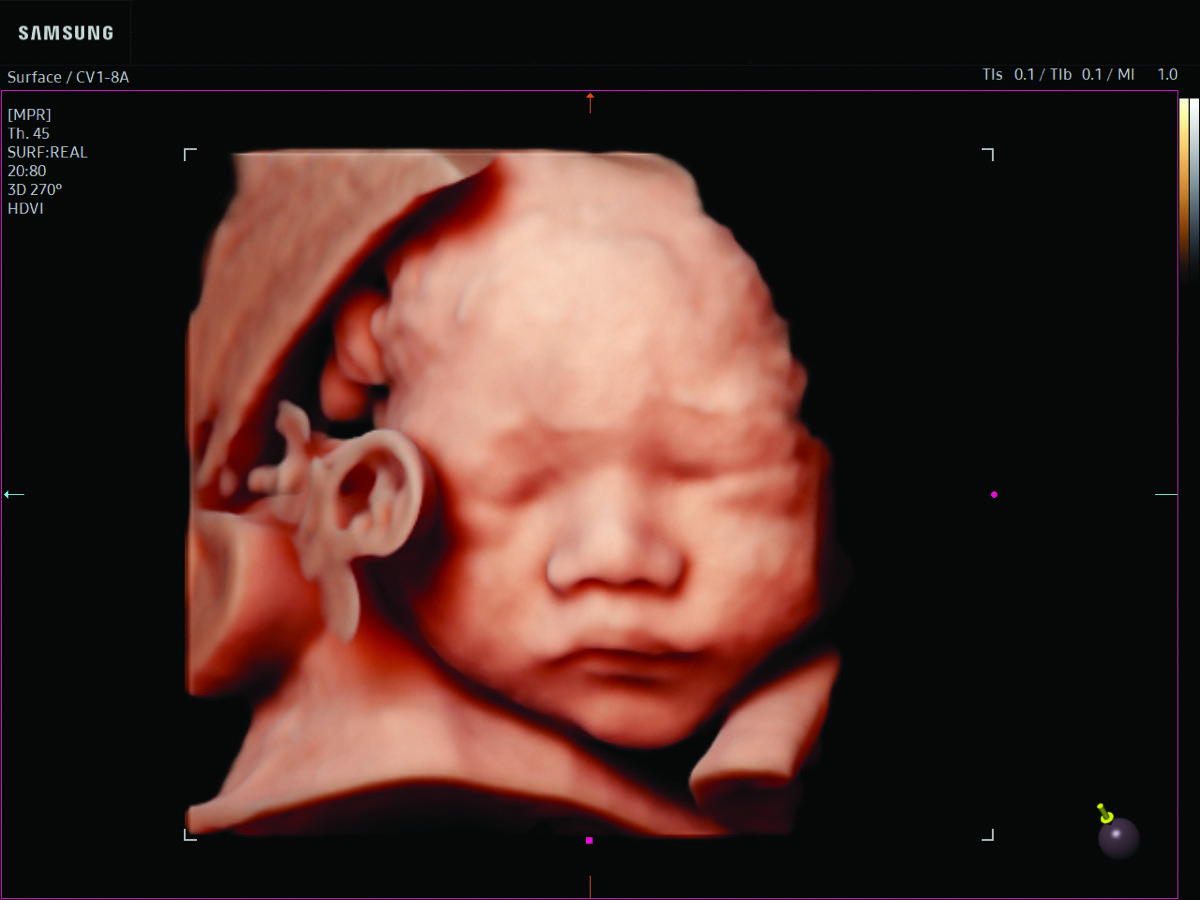

Comprehensive, advanced and expert MFM care for high-risk pregnancies

- Fetal anomalies